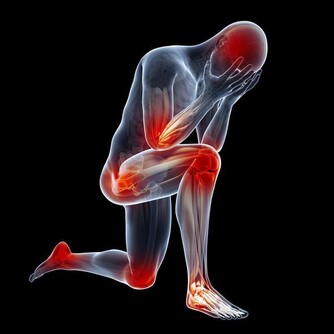

無名指對應人體三焦經,所以經常偏頭痛、肩頸痛的人,說明氣血運行不好,可以刮刮無名指。 脫髮 刮小指

中醫認為人的手背經絡對應人體腰部,所以經常腰痛、腰酸的人,應該多拍拍手背。一手手掌拍另外一隻手的手背,交替拍即可。 這些方法簡單、實用,建議大家現在就做一次,刮刮手指,再拍拍手掌,每個動作重複20次,你一定會覺得身體清爽許多。 「新老人(微信號xinlaoren)」是中國最大的中老年人網站「楓網」官方微信,我們致力於關注您的健康和生活,為您提供最可靠、最精緻的閱讀服務。